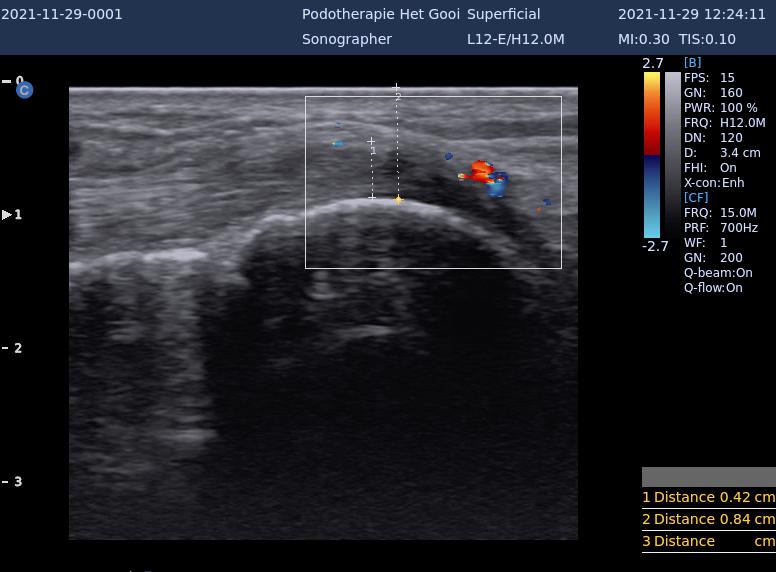

echo tibialis anterior